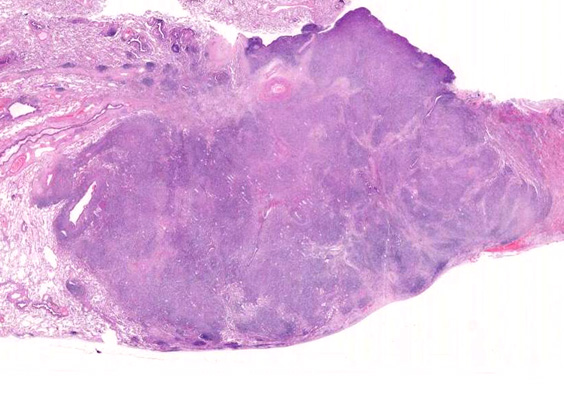

VATS採取標本肉眼腫瘤割面像腫瘤組織ルーペ像

病理組織所見